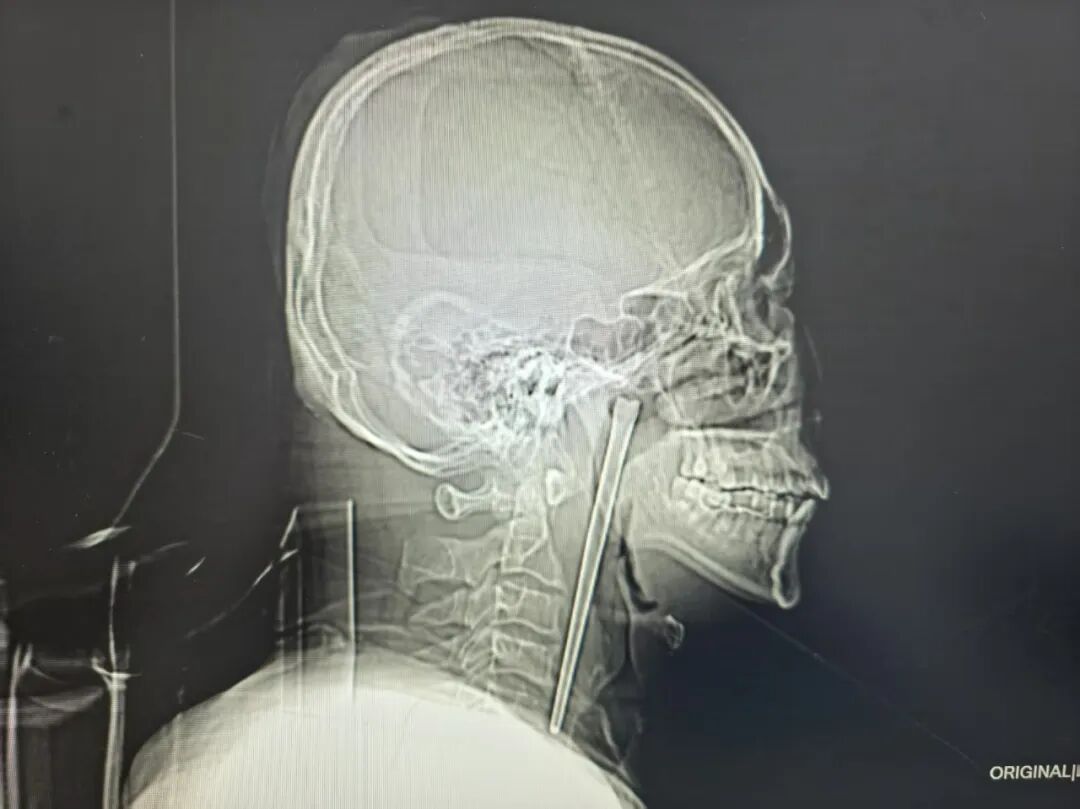

近日,大连理工大学附属中心医院耳鼻咽喉头颈外科接诊了一位特殊患者,46岁的王先生因咽部突发疼痛、异物感难忍就诊,而检查结果让所有人都大吃一惊,一根长达12厘米的金属筷子竟在他的咽部“藏”了整整8年。

检查结果清晰显示,王先生右侧咽后壁上方软腭后侧有一根金属筷子嵌入其中,外露部分约3厘米。

考虑到王先生8年前因顾虑颈部切开手术的创伤而放弃治疗的过往,医生为其定制经口腔取异物的微创手术方案,无需颈部开刀的治疗方式。最终将这根长达12厘米的不锈钢筷子完整取出。整个手术过程十分顺利,术中出血量极少,未出现任何手术并发症,让患者和家属悬着的心终于落地。